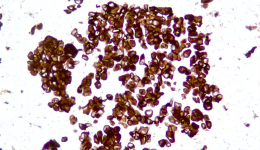

| Description | CLDN18.2是Claudin蛋白質(zhì)家族的一員,位于細(xì)胞膜表面,Claudin18.2(CLDN18.2)表達(dá)具有特異性。其作為Claudins蛋白的一個(gè)亞型,在正常組織中僅表達(dá)于分化的胃黏膜上皮細(xì)胞。在胃癌、食管癌和胰腺癌等多種腫瘤中表達(dá),并且不僅限于原發(fā)病灶,在轉(zhuǎn)移灶中也有表達(dá)。目前臨床研究中使用的檢測方法均為免疫組化。 |

| 示例 | ![]()  |

| IHC染色結(jié)果 | |